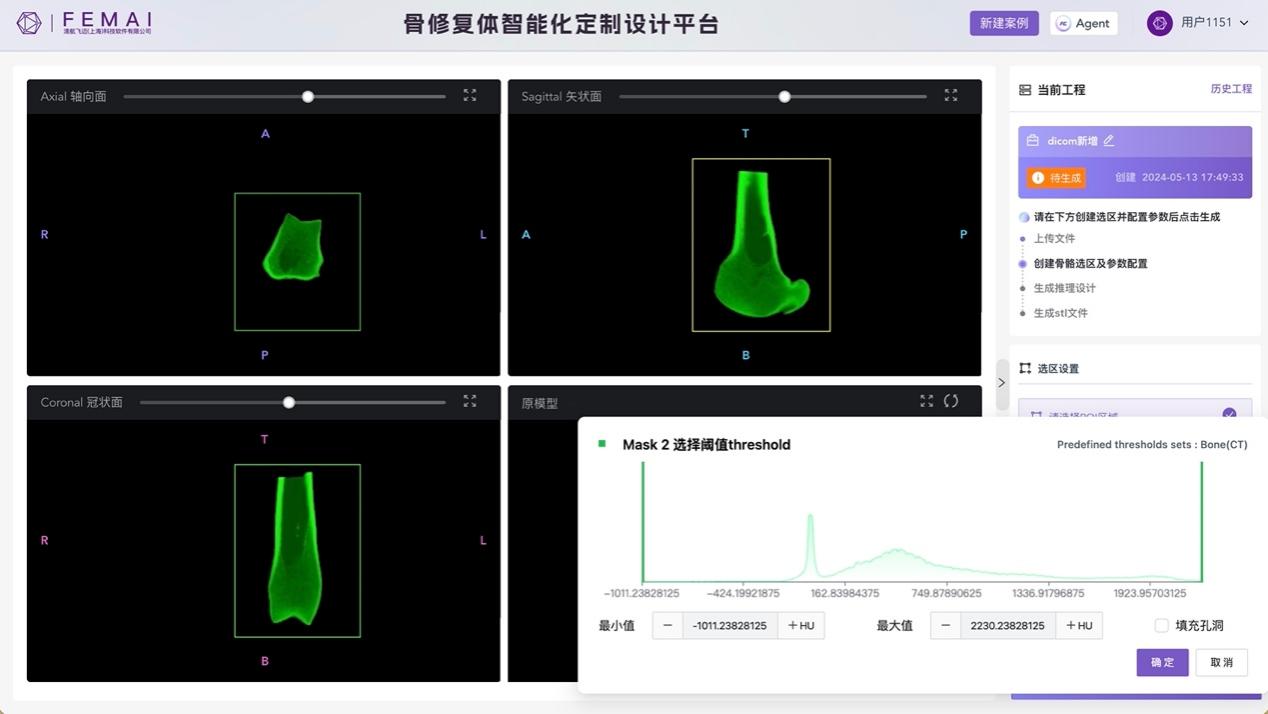

图2 智能设计系统通过Hu值切分法分离需设计骨组织结构

传统定制骨植入物制造需经历医学影像分析、CAD建模、CAE验证以及3D打印等独立分散步骤,通过大量人工完成全流程分析与设计,设计周期通常为1-7天,对尤为注重时效的急重创伤性损伤的治疗造成一定滞后,增加患者截肢概率。该成果针对传统骨植入物设计制造时间周期长的难点,通过精巧的神经网络模型搭建,使定制假体骨设计过程全面自动化,实现从数小时缩减至1分钟内完成的突破性时效飞跃,为骨缺损急症重症病例诊疗提供更优路径。

该成果率先突破从低分辨率CT影像重建高精度骨结构的一大难点,解决了松质骨各向异性力学性能精准适配问题,并在此基础上建立起人体骨医学影像-力学性能数据库。

通过综合运用影像学、临床医学、力学、人工智能技术,该成果建立了骨小梁的复杂结构与临床医学影像之间的关系,通过力学参数的跨尺度计算,搭建人体骨组织的高精度数字模型,实现以数据驱动的方法训练神经网络,进行骨组织结构设计,设计出匹配自然骨的个性化人工骨,最终实现骨修复体全方位的性能优化。